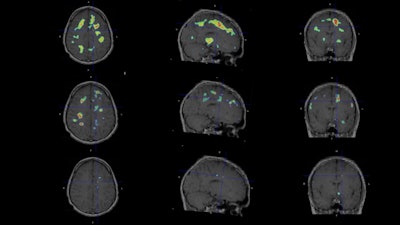

Individualized parametric z-score maps of the brain showing glial activity load in the brain, compared among individuals with secondary progressive MS (SPMS) (top row), relapsing-remitting MS (RRMS) (middle row), and a healthy control (HC) (bottom row) in transaxial, sagittal, and coronal sections. Image courtesy of Clinical Nuclear Medicine.

The researchers performed F-18 PBR06 PET scans on 22 patients with MS and eight healthy controls. They measured the “glial activity load” on the scans and compared results among patients with MS and healthy controls, as well as between individuals with MS on high-efficacy disease-modifying therapies (n = 13) and those on no or lower-efficacy treatments.

According to the analysis, glial activity on F-18 PBR06 PET scans was higher in patients with MS than healthy controls in cortical gray matter (+33%) and white matter (+48%). In addition, among MS patients treated with high-efficacy disease-modifying therapies, glial activity load was linked with increased cortical atrophy.